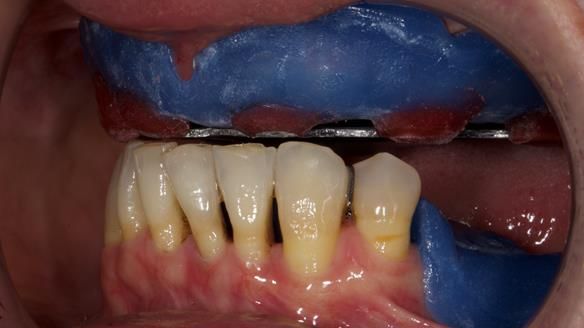

She had previously suffered from generalised periodontitis – stage IV, grade C, currently stable, with reduced attachment across the upper arch.

By the time she came to me, her periodontal condition was stable — but the aesthetics in the upper jaw were very poor.

We provided her with an immediate upper denture (Mk 1), followed by a definitive metal-based upper denture (Mk 2). A lower removable partial denture was discussed, to be made only if needed once the upper treatment was complete. However, at review, this wasn’t necessary — Adnana had excellent neuromuscular control and function, even with a shortened dental arch (SDA).

- Immediate denture (Mk 1) fitted the same day the teeth came out

- Definitive denture (Mk 2), metal-based and custom-designed for her face

- A restored smile, restored lip support, and a patient who owned the journey